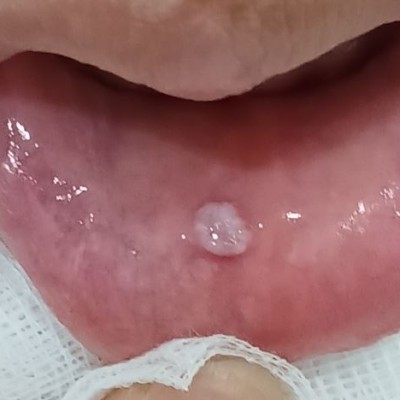

입술 안쪽 점액낭종 제거 N새글 입술 안쪽 점액낭종 제거입니다. 구강외과 전문의가 수술합니다. ---------------------------..